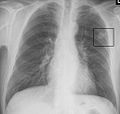

Der Unterschied zwischen der überlagerungsfreien Darstellung in der medizinischen Tomografie und einer Projektionsabbildung ist in den nachfolgenden Abbildungen illustriert. In Projektionsverfahren wie der Radiografie (gewöhnliche Röntgenuntersuchung) wird ein Schattenbild aufgenommen, auf dem sich mehrere Strukturen überlagern, wenn sie im Strahlengang hintereinander liegen. Beispielsweise überlagern beim konventionellen Röntgenbild die Weichteile der vorderen und hinteren Brustwand und die knöchernen Strukturen des Thorax die Lungenstrukturen. Dies würde die Diagnose eines Lungentumors (z. B. Bronchialkarzinom) erschweren. Jedes CT- oder MRT-Schnittbild vom Thorax zeigt dagegen nur eine 0,5 bis 10 mm dicke Schicht, die praktisch überlagerungsfrei ist.

-

Röntgenbild (Projektionsbild) eines kleinen peripheren Bronchialkarzinoms im linken Oberlappen -